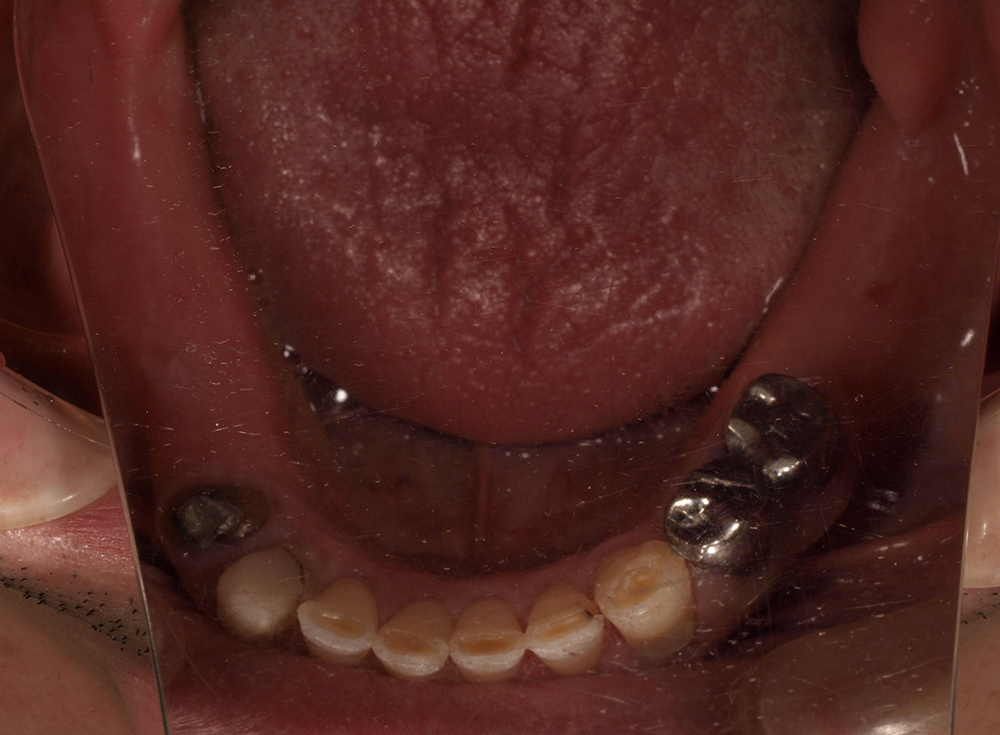

55歳 男性

- 主訴

- 前歯でしか咬めなく、食事を採るのに非常に困難で辛い

- 処置内容

- 上顎6本、下顎3本

- 治療費用

- 上顎:約230万(税込)下顎:約120万(税込)

- 治療期間

- 上顎:1年(仮歯まで8か月)下顎:8か月(仮歯まで5か月)

- リスク

- 上部構造物、仮歯の破折、術後の腫れ(3日)、人工歯根脱落リスクがあります